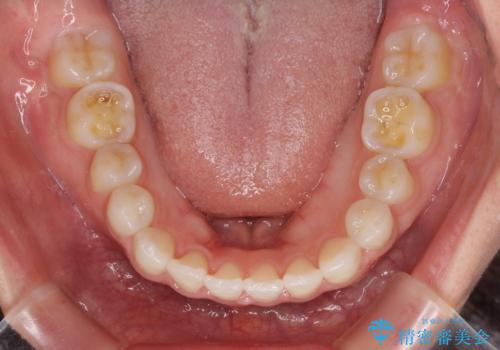

- ハーフリンガル

- 前歯のデコボコや八重歯、舌癖による開咬を気にして来院された患者様です。

目立たない装置を希望されたので、上顎が裏側装置のハーフリンガルを選択し、上顎小臼歯1本を抜歯して、補助装置を併用して矯正治療を行うこととしました。

補助装置を事前に使用したことで、あっという間に八重歯が改善し、ハーフリンガルにしては1年半もかからずに治療を終えることができました。